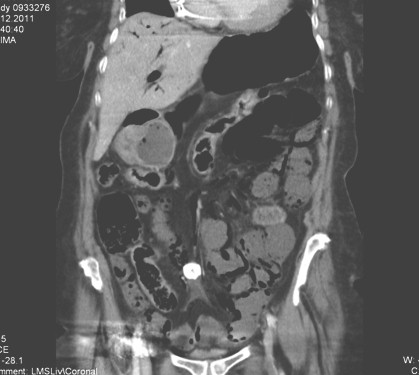

Allí se realiza TAC abdominal con contraste que evidencia un defecto de repleción en arteria mesentérica superior. Asas de ID dilatadas con neumatosis intestinal y aire en sistema portal y vasos mesentéricos secundario a infarto y necrosis intestinal.

Calcificación mesentérica compatible con adenopatía o tumor carcinoide. Dilatación del colédoco, quistes renales, infiltrados bibasales pulmonares (figura 2).

Como conclusión: infarto intestinal con oclusión de la arteria mesentérica con stop vascular superior proximal a bifurcación aorto-mesentérica, con signos indirectos de isquemia evolucionada de todo el intestino delgado (aerobilia, neumatosis intestinal con preservación únicamente del marco cólico, gas libre intravascular mesentérico) (figura 1).

Figura 1. Aerobilia, neumatosis intestinal con preservación únicamente del marco cólico, gas libre intravascular mesentérico

Figura 2. Defecto de repleción en arteria mesentérica superior. Asas de ID dilatadas con neumatosis intestinal y aire en sistema portal y vasos mesentéricos secundario a infarto y necrosis intestinal.